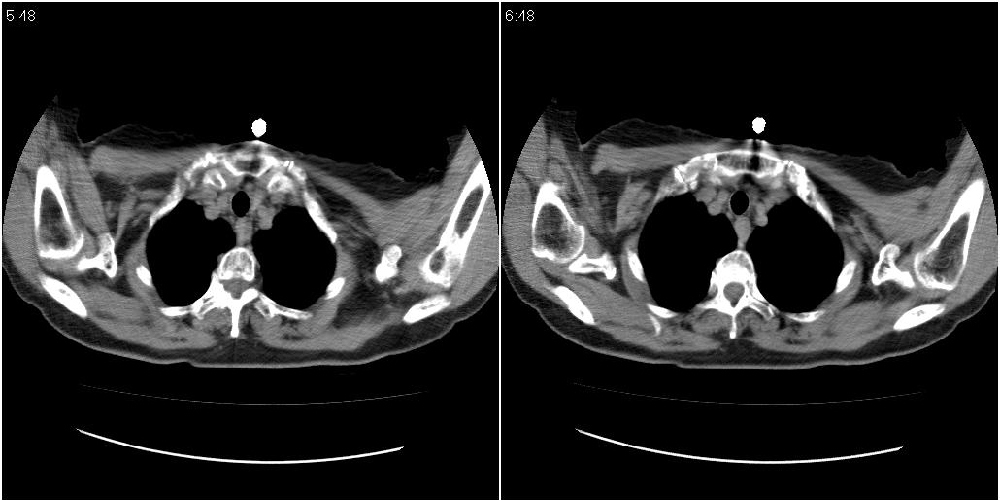

女性,72岁。去年9月份发现肺部病变,诊为肺结核并进行正规治疗至今,但复查后发现ct表现几乎没有变化。

右侧中叶支气管明显狭窄,建议行纤支镜检查!

右中间段支气管局限性狭窄,右中叶支气管亦稍显狭窄,但并未见明显占位表现,半年多了,无变化也许是好事,可能为炎性狭窄,建议继续随访。

双肺继发型tb并右中叶内膜tb,轻度支扩,左下胸膜肥厚粘连。

双肺继发性肺结核并右肺中叶节段性肺不张,左下胸膜肥厚粘连。

右肺中叶节段性肺不张,考虑结核或慢性炎症,建议做纤支镜检查。